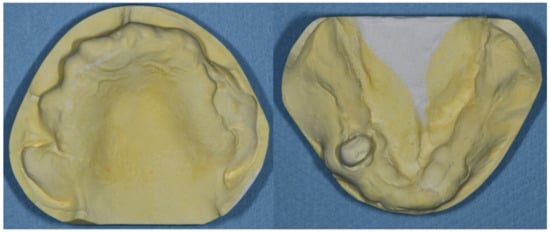

After the treatment, the patient could eat soft food with the dentures. The pressure-sensitive sheet kit (Dental Prescale II, GC Corporation, Tokyo, Japan) indicated the increment of occlusal contact points (Figure 5).

Figure 5. Pressure-sensitive sheet showing the occlusal contact points at the maximal cuspal position. The left image shows the contact point before the adjustment. The right image shows the increase in the contact points after selective grinding.